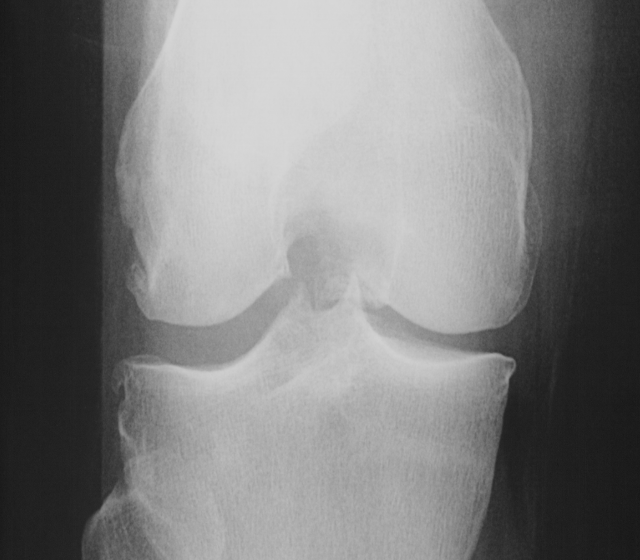

The data used for the experiments and analysis in this study are bilateral PA fixed flexion knee X-ray images. Figure 3 shows some samples of knee X-ray images from the dataset. Due to variations in X-ray imaging protocols, there are some visible artefacts in the X-ray images (Figure 3).

Refer to caption

Figure 3: Samples of bilateral PA fixed flexion knee OA radiographs.

The datasets are from the Osteoarthritis Initiative (OAI) and Multicenter Osteoarthritis Study (MOST) in the University of California, San Francisco. These are standard public datasets used in knee osteoarthritis studies.